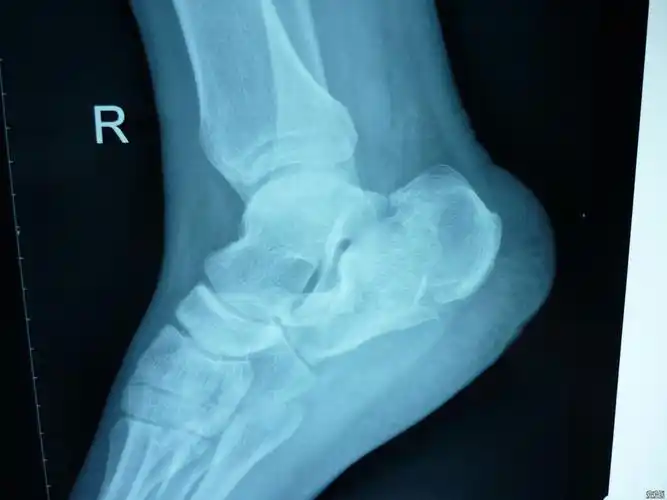

患儿,男,11岁,跟骨骨骺炎,跟骨侧位片可见跟骨骨

跟骨骨折病例

右足跟骨骨折